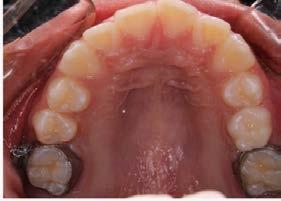

Caso clínico

Paciente femenino de 49 años de edad la cual acude a la consulta por odontalgia en segundo molar superior derecho, presenta obturación temporal y ausencia clínica de tercer molar superior

derecho (Figura 1). Especialista en endodoncia solicita cone beam en donde se visualiza lesión periapical extensa que involucra segundo y tercer molar ipsilateral y engrosamiento de la mucosa del seno maxilar sugerente de sinusitis maxilar crónica y su cercanía

con el tercer molar de dicha estructura (Figura 2).

Como antecedentes de importancia, la paciente refiere tratamiento previo por otorrinolaringología sin mejoría alguna, presentando rinorrea y obstrucción nasal constante ocasionando hiposmia, pero no correlacionándolo con una causa de origen dental.

Figura 1. Fotografía oclusal.